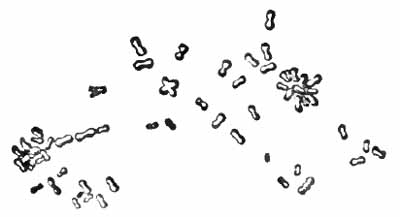

(2) Staphylococcus and Streptococcus (p. 262).—One or both of these organisms is commonly present in company with the tubercle bacillus in the sputum of advanced phthisis (Plate II, Fig. 2). They are often found in bronchitis, catarrhal pneumonia, and many other conditions.

(3) Pneumococcus (Diplococcus of Fränkel).—The pneumococcus is the causative agent in nearly all cases [p. 36] of croupous pneumonia, and is commonly found in large numbers in the rusty sputum of this disease. It is sometimes met with in the sputum of catarrhal pneumonia, bronchitis, and tuberculosis. It has been found in the saliva in health. Pneumococci are about the size of streptococci. They are ovoid in shape, and lie in pairs, end to end, often forming short chains. Each is surrounded by a gelatinous capsule, which is its distinctive feature (Fig. 9). Diplococci without capsules are common in the sputum, but have no special significance.

| FIG. 9.—Diplococcus pneumoniæ in the blood (Fränkel and Pfeiffer). |

Recognition of the pneumococcus depends upon its morphology, the fact that it is Gram-staining, and the presence of a capsule. Numerous methods for staining capsules have been devised, but few are satisfactory. Buerger's method is excellent. It is especially useful with cultures upon serum media, but is applicable also to the sputum. Smith's method usually gives good results, as does also the more simple method of Hiss (p. 263). The sputum should be fresh—not more than three or four hours' old.